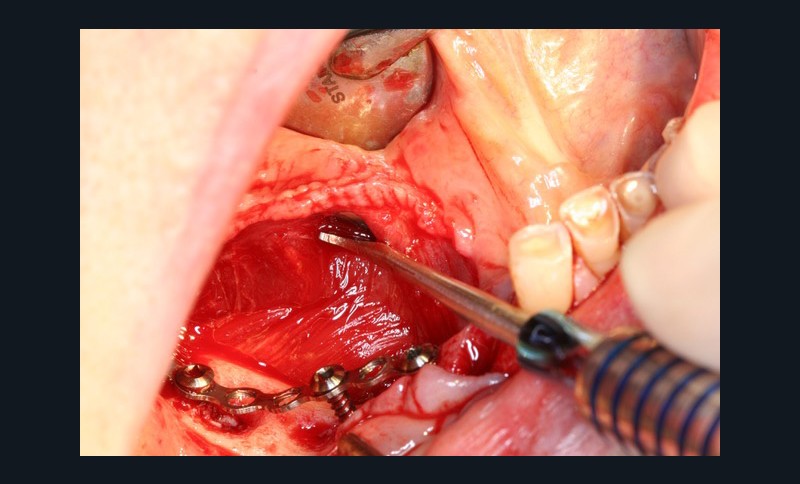

Dans la seconde partie de la soirée, le Docteur Surmenian, qui a intégré ces principes biologiques à ses protocoles d’augmentation osseuse, a pu développer ses nouvelles propositions thérapeutiques et leur apport comparativement aux procédures conventionnelles. Sa présentation, dont le titre interroge nos habitudes énonce l’ambition du concept chirurgical : « Faut-il tout changer pour simplifier et fiabiliser les augmentations osseuses ? » En convenant que les augmentations tridimensionnelles de la région postérieure mandibulaire constituent un défi thérapeutique que les techniques de greffes osseuses autologues en coffrage permettent de relever, le conférencier a rappelé à l’assistance toutes les difficultés associées à cette procédure. L’approche moins invasive suivie repose sur le choix de techniques de régénérations osseuses au moyen de particules cortico-spongieuses allogéniques et en respectant les fondamentaux biologiques tissulaires développés en première partie de soirée. Le recours à une plaque d’ostéosynthèse (Fast system®) maintenue à distance du site grâce à un ingénieux filetage résidant à la tête des vis de fixation offre une structure aisée à installer sur la crête à augmenter. Le dispositif rigide facilement stabilisé préserve le matériau venant combler l’espace du défaut, des pressions et tensions sus-jacentes. Le comblement est assuré à l’aide de particules cortico-spongieuses d’os allogène amalgamées à du PRF qui leur confèrent une consistance compacte (sticky bone).

La troisième approche consiste à libérer les lambeaux afin d’obtenir la laxité nécessaire à une fermeture sécurisée du site augmenté. Le relâchement du lambeau lingual décollé jusqu’à la ligne oblique interne est obtenu par un « brossage » apico-coronal de sa face interne à l’aide d’instruments spécifiques. Celui du lambeau vestibulaire repose sur le même principe (soft brushing). Les sutures finalisent la procédure en répartissant les tensions de repositionnement des lambeaux à distance (apical matress) et à proximité des berges de l’incision crestale. Le port des prothèses adjointes est prohibé et les sutures sont déposées 4 à 5 semaines après la chirurgie. Lors de la mise en place des implants (environ 4 mois après l’augmentation osseuse), le Docteur Surménian applique le principe de limitation de la compression des tissus durs en surdimensionnant son ostéotomie (surtout au niveau cortical). Ce principe l’a amené à sélectionner un implant (Anyridge® de Megagen) présentant une stabilité primaire majorée sans pour autant rechercher une élévation du couple d’insertion (signe de compression tissulaire).